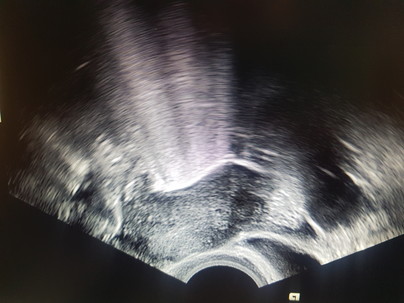

HyFoSy - Hysterokontrastsalpingographie: Untersuchung zur Prüfung der Durchgängigkeit der Eileiter

Als Ihre Frauenärztin möchte ich gerne eine komplette Abklärung anbieten. Die Eileiter werden mittels Kontrastmittel-Ultraschall untersucht.

• Mit Kontrastmittelschaum